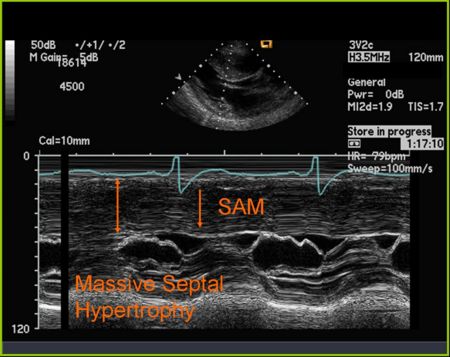

M Mode in Hypertrophic Cardiomyopathy

- Septal hypertrophy

- Systolic anterior motion (SAM) of the anterior mitral valve leaflet

- Mid-systolic (premature) closure of the aortic valve due to outflow track obstruction